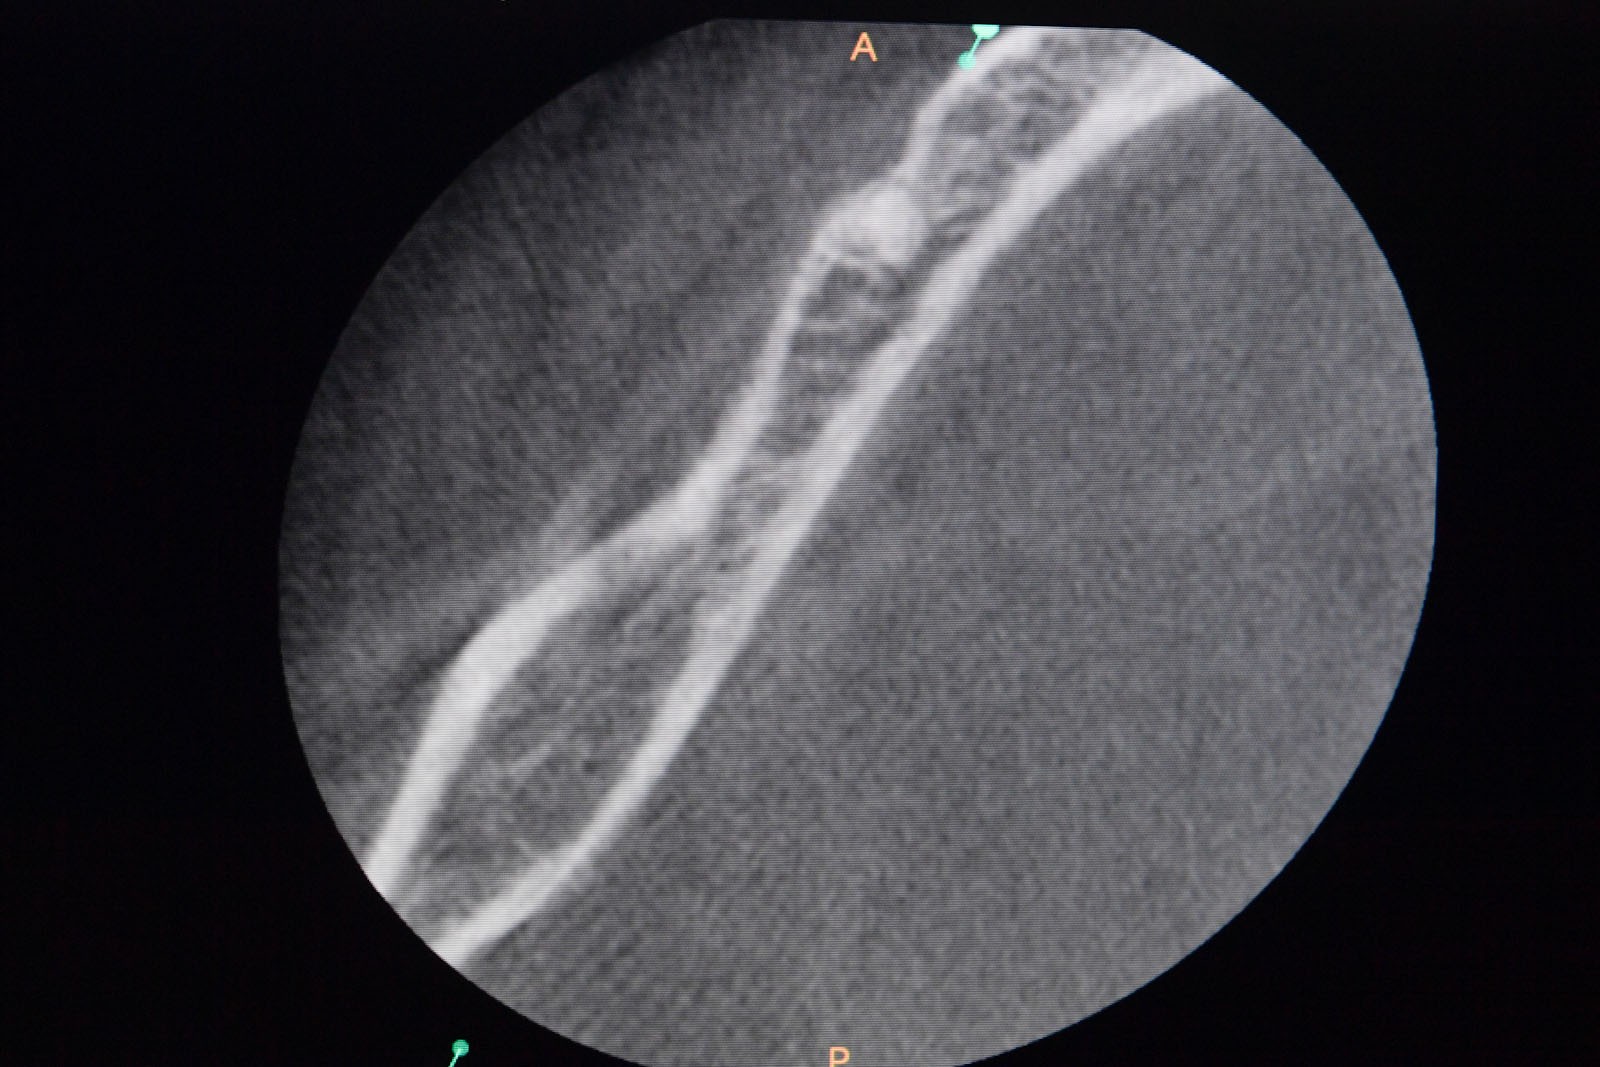

Przed podjęciem leczenia należy określić stopień zaniku kości szczęk oraz żuchwy. W tym celu przeprowadza się badanie kliniczne oraz odpowiednią diagnostykę obrazową pacjenta. Uwzględnia ona zdjęcie panoramiczne OPG jako podstawę dwuwymiarowego obrazowania podłoża kostnego oraz możliwe jest badanie tomograficzne CT lub bardziej precyzyjna tomografia stożkowa CBCT. Opcjonalnie wykorzystywana diagnostycznie tomografia pozwala na bardziej wnikliwą ocenę stopnia zaniku kości w trójwymiarowym, przestrzennym obrazie.

Zatoki szczękowe to symetrycznie umieszczone w kościach szczęk przestrzenie powietrzne, posiadające komunikację z jamą nosa. Średnio pojemność zatok wynosi 24 cm3, a ściany wyścielone są błoną śluzową (membrana Schneidera). Dno zatoki szczękowej stanowi wyrostek zębodołowy, w którym umieszczone są zęby, często zlokalizowane tuż pod cienką wyściółką zatoki. Statystycznie najwęższy obszar kostny w tej strefie zlokalizowany jest na wysokości zębodołów pierwszego i drugiego zęba trzonowego.

Ta szczególna metoda używana jest w obszarze dolnego łuku zębowego w sytuacji braku dostatecznej ilości kości na wysokość. Metoda stosowana jest w sytuacji rozległych zaników kostnych w bocznych odcinkach żuchwy, w której wprowadzenie implantów groziłoby uszkodzeniem gałązek nerwowych nerwów zębodołowych dolnych. Gałązki nerwowe biegną wraz z naczyniami krwionośnymi we wspólnej pochewce w kanałach kostnych, umieszczonych symetrycznie po obu stronach w trzonach żuchwy.

Technika polega na chirurgicznym ich przemieszczeniu, a przez to stworzeniu bezpiecznego miejsca dla wszczepienia implantów o odpowiednej długości, co gwarantuje ich stabilną pozycję. Stosuje się ją wraz z zabiegiem rekonstrukcji kostnej przy użyciu biomateriałów w formie granulatu i membran. Zabieg ten stosowany jest rzadko, jako alternatywa rozległych regeneracji kostnych. Wybierany bywa jako alternatywa operacyjna tylko w sytuacji, gdy konwencjonalne metody odbudowy kostnej są niewystarczające lub generują ryzyko braku skutecznej odbudowy kostnej celem wszczepienia implantu.

Precyzja projektu druku siatki bazuje na dokładności odwzorowania kształtu kości w stożkowej tomografii komputerowej CBCT, co zapewnia ich dobre przyleganie do podłoża kostnego oraz ogranicza powstawanie powikłań w postaci obnażania się siatek.